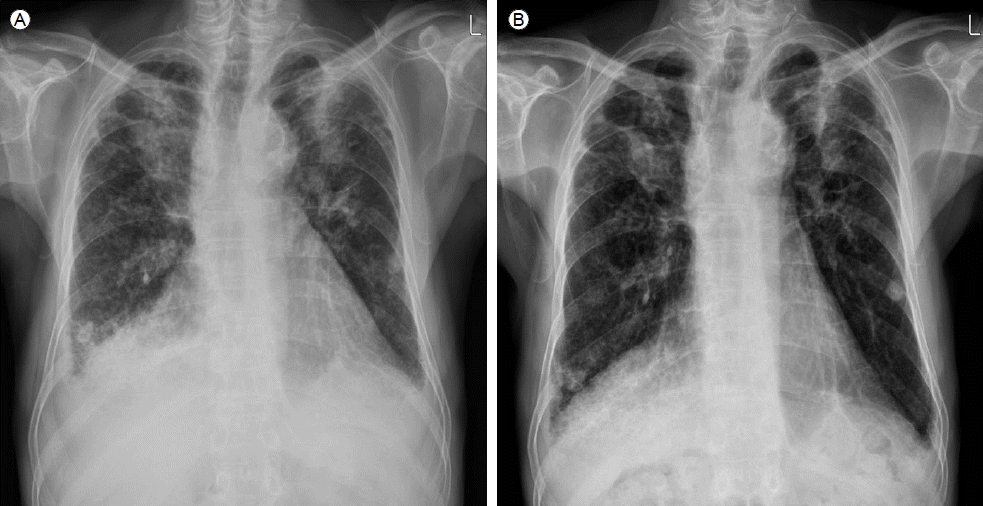

Figure 1.

The chest X-ray before treatment shows (A) diffuse, irregular infiltrations in the lung parenchyma bilaterally, and tumor-like lesions in both upper lobes. These findings were seen in previous chest films and had not changed. The pleura effusions at the costophrenic angles were new and the left cardiac border was bulging slightly. (B) After 4 weeks of steroid therapy, the costophrenic angle blunting had improved bilaterally and the cardiac border was slender.

류마티스성 흉막염과 심장막염이 발생하여 환자의 호흡곤란이 악화된 것으로 판단하고 프레드니솔론 0.5 mg/kg을 하루 한번 투여하기 시작하였다. 치료 시작 일주일 후 환자는 호흡곤란이 호전되었고, 프레드니솔론을 유지하면서 퇴원하였다. 4주 후 시행한 흉부방사선 사진에서는 치료 전과 비교하여 흉수가 감소한 소견을 보였고(Fig. 1B), 2개월 후 추적검사한 흉부 방사선단층촬영에서도 양측의 흉수가 거의 소실되고, 심장막액도 감소한 모습이 관찰되었다. 더불어 우하엽의 병변도 치료 전보다 호전되었다(Fig. 2B). 환자는 이후 6개월 동안 증상악화 없이 스테로이드 감량하며 경과관찰 중이다.